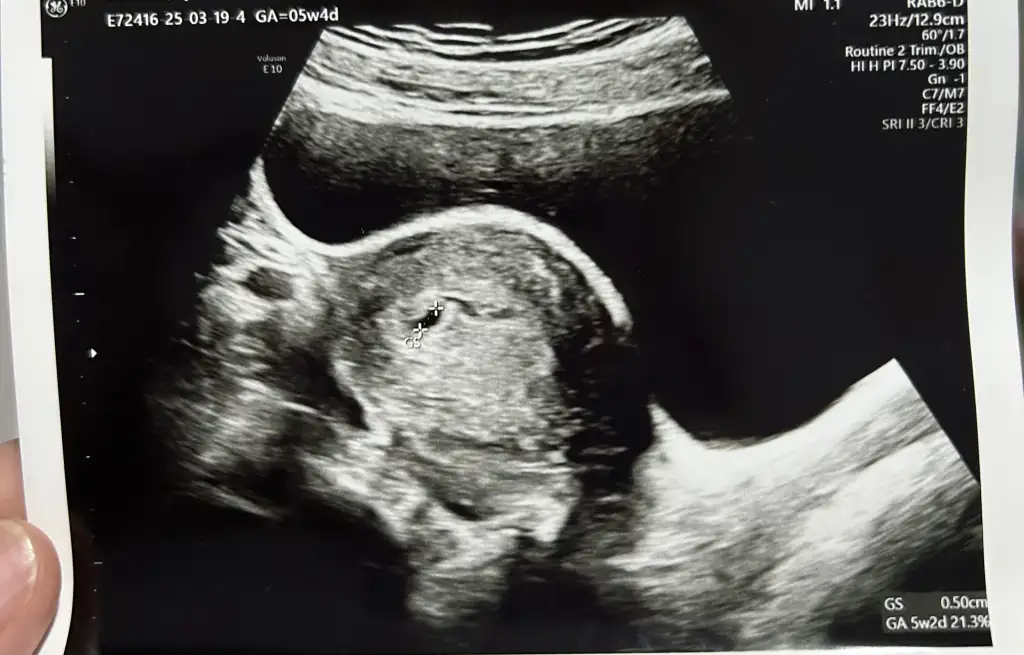

Sizce bebeğimin cinsiyeti nedir?

Vajinal ultrason yapıldı. 5 hafta 5 günlük.